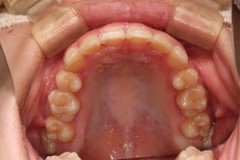

治療後

上下顎第一小臼歯の抜去後、カスタムメイド型アライナーによる治療をすすめました。

顎間ゴムとアンカースクリューの併用を必須としました。IPRの可能性についても提案しました。